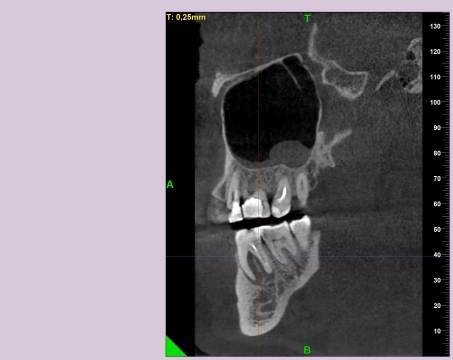

КТ от 28.05.2024

28_05.24(2).jpg.0ffa1febe861106733e1de830afbe6f4.jpg28_05.24-1(2).jpg.9c45d7be16aeed505bd413ce9bc6e69e.jpg28_05.24-2.jpg.a728a7d7e6213c1c8302b43adc89e4d0.jpg28_05.24-4(2).jpg.ac43f3448a3988c7006f74e1d0ce09da.jpg28_05.24-6(2).jpg.dd1fd85c6cc0fcd3d43bd9e71fc0d616.jpg28_05.24-8(2).jpg.885c8cb905445e9308f124fb9e5c616b.jpg28_05.24-9(2).jpg.6cceaaaa1b56d0967482c87b951fbe2d.jpg28.5.24-5(2).jpg.b2d79427a16769c9fd4f0d0911a9db8f.jpg28.5.24-7(2).jpg.f6c17f9820e72dc2708955a65a190b57.jpg28.0524-3(2).jpg.0aa9f153071766a340b428158a94ade8.jpg